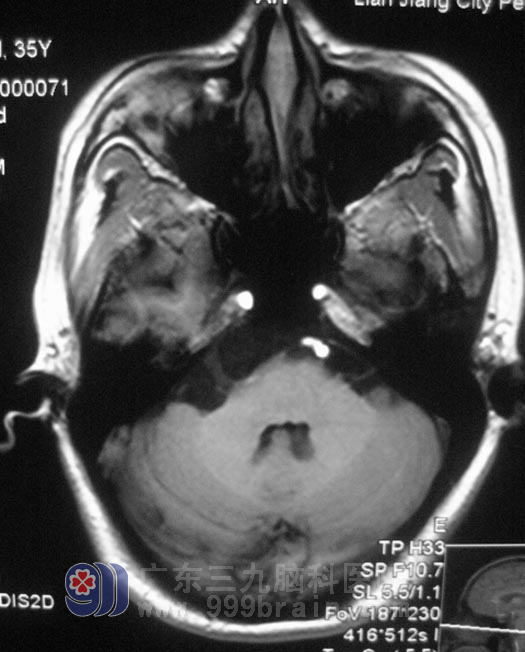

小张大约在两个月前开始出现右侧颜面部疼痛,呈放电样,持续约数分钟后自行缓解,每天发作数次,进食可诱发,喜爱的歌也不敢哼。当地医院以“三叉神经痛”治疗,口服卡马西平,但症状反复。当地上一级医院MR检查示“右侧桥小脑角区占位,考虑表皮样囊肿,大小约4cm×1.8cm”。小张自己在网上查阅了很多资料,了解到三叉神经痛方面的相关知识,最终决定在广东三九脑科医院三叉神经痛诊疗中心接受治疗。http://www.999brain.com/

鲁明主任通过MR弥散检查,考虑胆脂瘤可能。1月4日在全麻下行右侧乙状窦后入路桥小脑角区胆脂瘤切除术,术中见白色珍珠样肿瘤组织,位于右侧桥小脑角,质软,血供丰富,显微镜下分块切除,肿瘤与三叉神经粘连紧密,小心分离后完整保留三叉神经;术中对面神经、听神经保护完好,手术顺利结束。术后一小时,小张醒后诉右侧颜面部放电样疼痛消失。没有出现面瘫、嘴角歪斜等术后并发症。术后病理结果为:胆脂瘤。

▲手术前